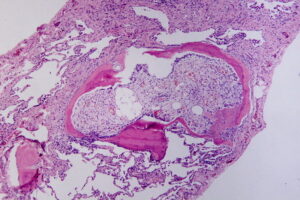

Dr. Kristin Foley recently published the article, “Histopathology of Periarticular Non-Hereditary Heterotopic Ossification” in the journal Bone, on Dec 7 2017. It is an histological examination of how injury can cause formation of bone near and within joints. This research was conducted in part by Dr. K. Foley during her work at University of Pennsylvania. It is the first systematic evaluation of the predominant histopathological findings associated with multiple forms of non-hereditary heterotypic ossification showing they share a common formation mechanism.